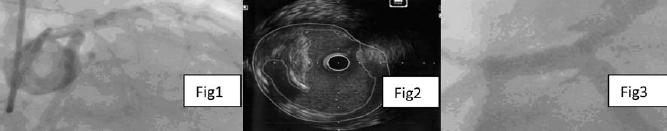

Método: paciente de 79 años, sexo masculino, con antecedentes de DM tipo II y tabaquista. Consultó por dolor retroesternal de tipo opresivo irradiado a cuello y elementos neurovegetativos. En el ECG se observó supradesnivel del ST (7 mm) anterolateral. Se derivó a CACG a las 3 h de iniciado el evento.

Resultado: en la CACG se observó la ADA ocluida en su tercio medio y una lesión del TCI de difícil estadificación y morfología atípica (figura 1). Se predilató la lesión y posteriormente se implanta stent sobre la lesión oclusiva. Se completa la valoración mediante el uso de IVUS en donde se observa una lesión moderada del TCI de aspecto ulcerado en su tercio medio (figura 2). A continuación se realizó ATC de dicha lesión con implante de stent (figura 3). El paciente presentó buena evolución clínica. Cumple prevención secundaria.

Conclusión: hay situaciones en la que la angiografía convencional encuentra limitaciones para definir las características morfológicas y la severidad de una lesión. El uso de IVUS clarifica estas características, guía en el tratamiento y logra una optimización de la técnica de ATC con stent.